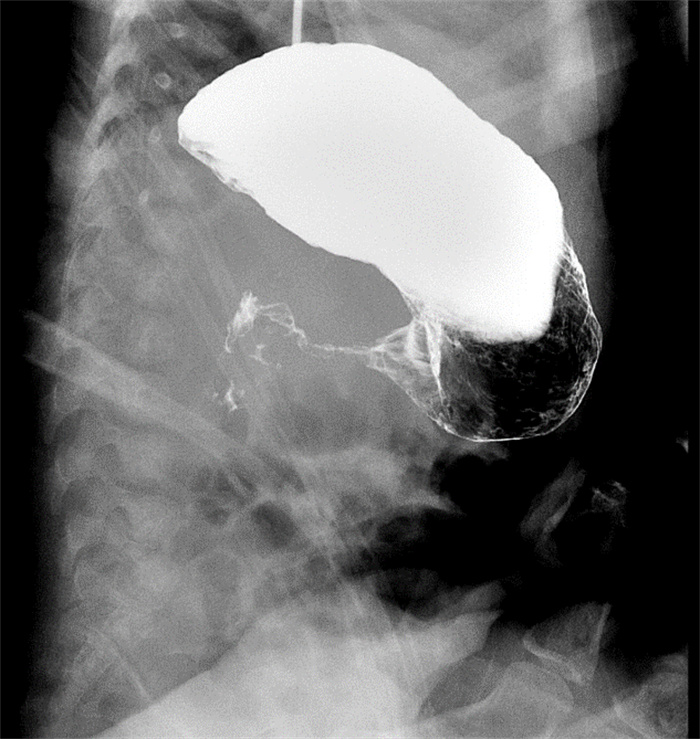

術(shù)前消化道造影提示幽門狹窄

入院后,兒科團(tuán)隊完善彩超檢查,提示軒軒為幽門肥厚,全消化道造影提示胃幽門部狹窄,考慮先天性肥厚性幽門狹窄。兒科副主任李淑歡立即組織科內(nèi)討論并請小兒外科團(tuán)隊參與會診討論治療方案。